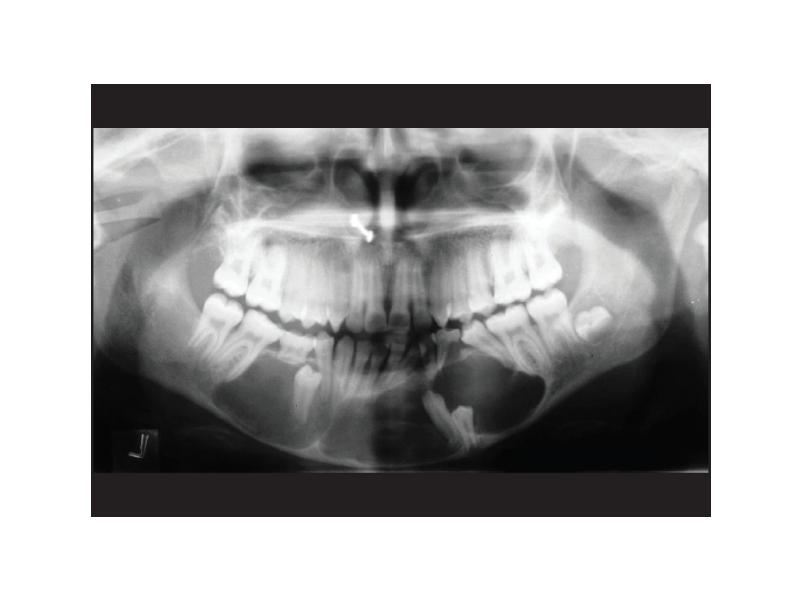

- 21. Макроскопическая картина Локализуется чаще всего в зоне формирующегося зачатка 3-го нижнего